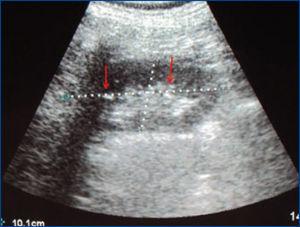

Presentamos el caso de un paciente masculino, de 33 años de edad, con antecedente de hipopotasemia sin estudio hace 2 años, que acude a Urgencias con 10 días de debilidad progresiva de extremidades, fatiga, astenia, mialgias, negando síntomas urinarios. Se automedica con sales de potasio sin mejoría, por lo que decide buscar ayuda médica. Al examinarle, se encontró con presión arterial de 119/66 mmHg, frecuencia cardíaca de 67 latidos/minuto, frecuencia respiratoria de 22 ciclos/minuto, temperatura de 37 °C, con debilidad en 4 extremidades 3/5 y reflejos tendinosos disminuidos. Sus laboratorios al ingreso reportaban una creatinina sérica de 1,36 mg/dl, sodio sérico de 137 mEq/l, potasio de 3,2 mEq/l, cloruro de 114 mEq/l, calcio de 8,8 mg/dl, fósforo de 3,5 mg/dl, magnesio de 2,2 mEq/l, bicarbonato de 19 mEq/l, pCO2 de 30 mmHg, PH venosa de 7,36, lactato de 0,8 mEq/l, albúmina sérica de 4,1 g/dl, orina con pH 6,5 sin glucosuria y un sedimento urinario con leucocituria y eritrocituria mínima, sin nitritos, ni bacterias evidentes a la microscopía, y proteinuria de 550 mg/24 horas. Se envió a cultivar orina; nivel de complementos normales, perfil viral negativo para virus de la inmunodeficiencia humana y virus de la hepatitis B y C. Se realiza un ultrasonido renal con imágenes hiperecogénicas sugestivas de calcificaciones medulares (figura 1), calciuria de 4,2 mg/kg/día, anión gap urinario positivo (sodio 58 mEq/l, potasio 16 mEq/l, cloro 23 mEq/l), fracción excretada de potasio de 12 %, fracción excretada de bicarbonato 7 %, pero un PH urinario que no logró reducirse a < 5,5 en un período de más de 8 horas y reducción del gap urinario, aunque sin llegar a negativizar (sodio 47 mEq/l, potasio 12 mEq/l, cloro 43 mEq/l) luego de una administración oral de cloruro de amonio, por lo que se catalogó como una acidosis tubular renal distal (ATRD) (tipo 1). Al reportarse urocultivo negativo, se realiza biopsia renal percutánea, la que reportó nefritis tubulointersticial crónica con nefrocalcinosis intratubular e intersticial (figura 2), por lo que se inició tratamiento con prednisona a 1 mg/kg/día y citrato de potasio a 1 mEq/kg/día. Una semana después, existiendo reducción en leucocituria, se reportan estudios inmunológicos con anticuerpos antinucleares positivos, con un título de 1:2560, anti-SSA y anti-SSB positivos. Se realizó test de Schirmer, que resultó positivo, curiosamente sin referir síntomas de ojo seco. En su seguimiento por consulta externa a las 16 semanas, con prednisona 5 mg/día, muestra una creatinina de 0,88 mg/dl, reducción del requerimiento de sales de potasio manteniendo niveles de potasio normales, pH urinario alrededor de 5, calciuria de 3,9 mg/kg/día, anión gap urinario negativo (sodio 21 mEq/l, potasio 8 mEq/l, cloro 47 mEq/l), con ausencia de leucocituria, eritrocituria y proteinuria.

Figura 1. Ultrasonido renal con hiperecogenicidad medular sugestiva de calcificaciones.